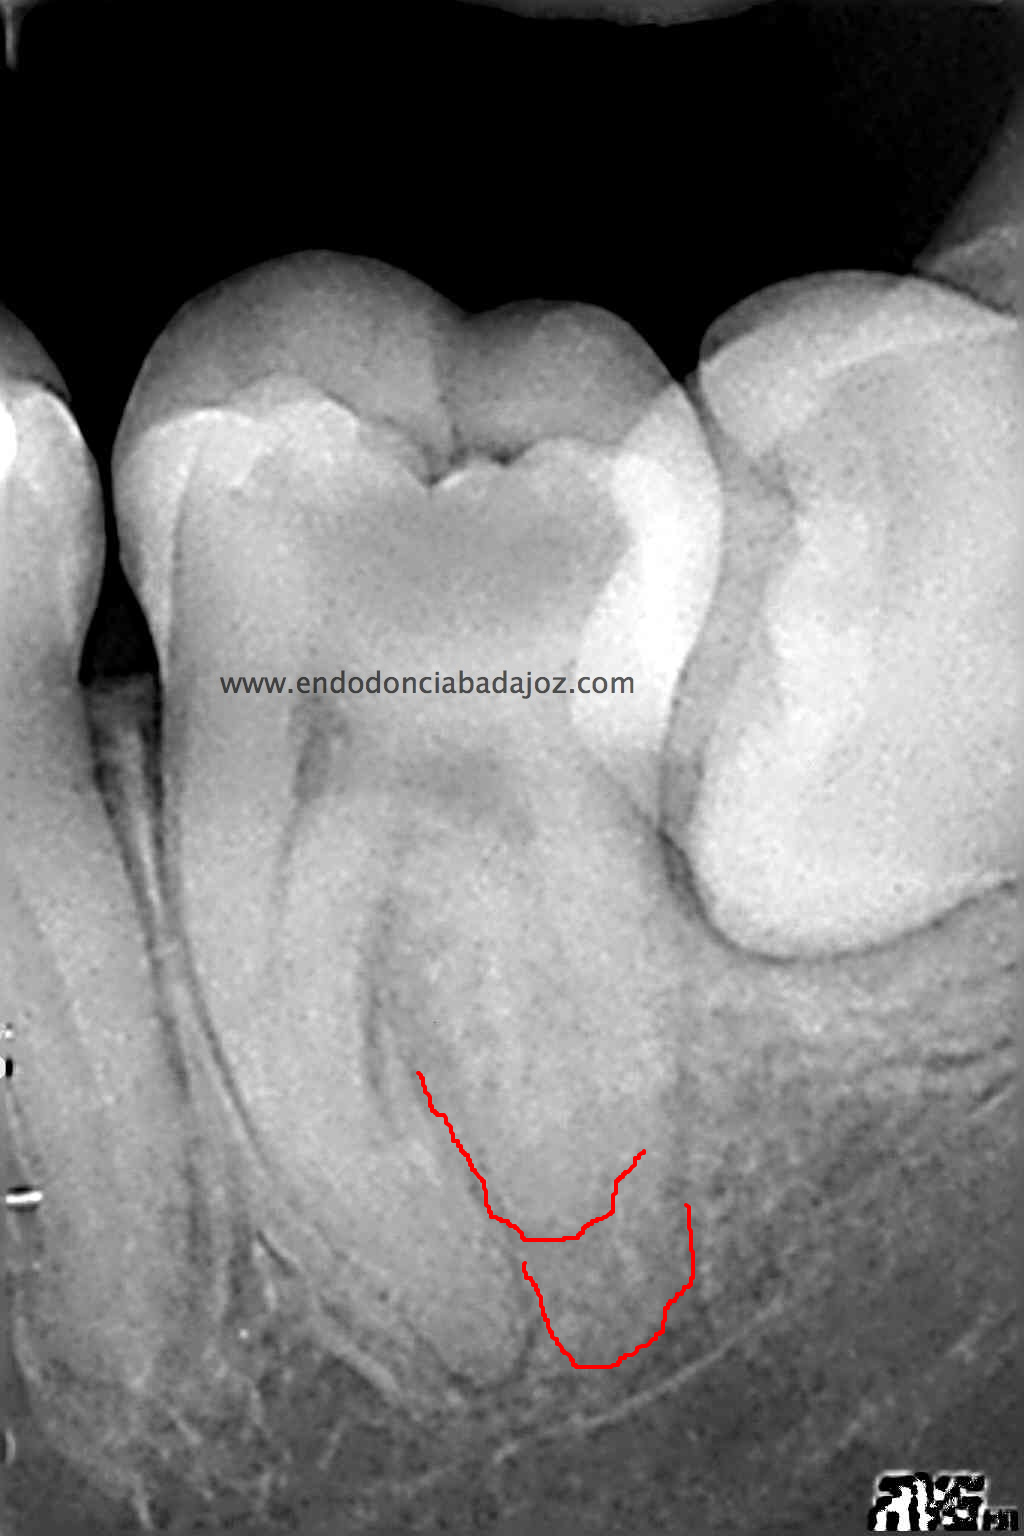

Se trata de un caso que ,a priori, traté como un 3.7 de tres conductos:

Después de haber instrumentado con un sistema Protaper, y habiendo estandarizado el conducto en un 25mm en apical y una conicidad del 6% con limas K3. observé que el conducto Distal presentaba otro conducto Disto-Vestibular cuya entrada estaba en la pared del conducto Disto-Lingual tratado, bastante complicado de trabajar.

Observando la Rx pude verificar y diferenciar las raices: